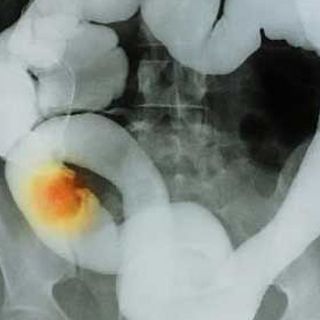

GUADALAJARA, JALISCO (06/AGO/2010).- Una investigación del Instituto Mexicano del Seguro Social (IMSS) concluye que la obesidad, junto con el consumo excesivo de carnes rojas y una vida sedentaria aumentan la posibilidad de desarrollar cáncer de colon.

La obesidad central, la que se concentra en el abdomen, es el principal factor de riesgo encontrado para el desarrollo de cáncer de colon, aseguraron los investigadores.

En el muestreo quedó de manifiesto que la ya referida obesidad central fue, con un 63.8 por ciento de presencia en las personas estudiadas, el factor de riesgo más importante como disparador del cáncer de colon.